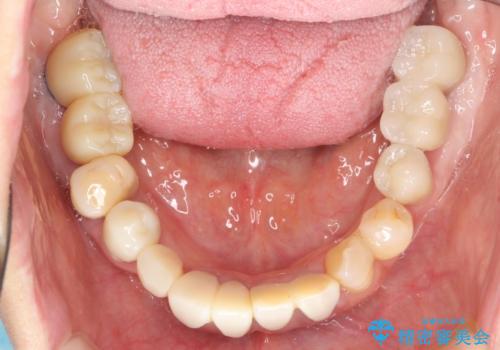

歯周病 全顎治療

- 前歯の見た目、入れ歯による噛めないことの改善を求めて来院されました。

検査により全顎的な歯周病治療、欠損のインプラント補綴、根管治療が必要な状態であることをお伝えし、治療を計画します。

失ってしまった機能を回復し、今後歯を失わないよう残せる歯に歯周病治療を行い、安定した咬合を確立することで長期的に問題なく噛めるような口腔内環境を達成できるようになると考えます。